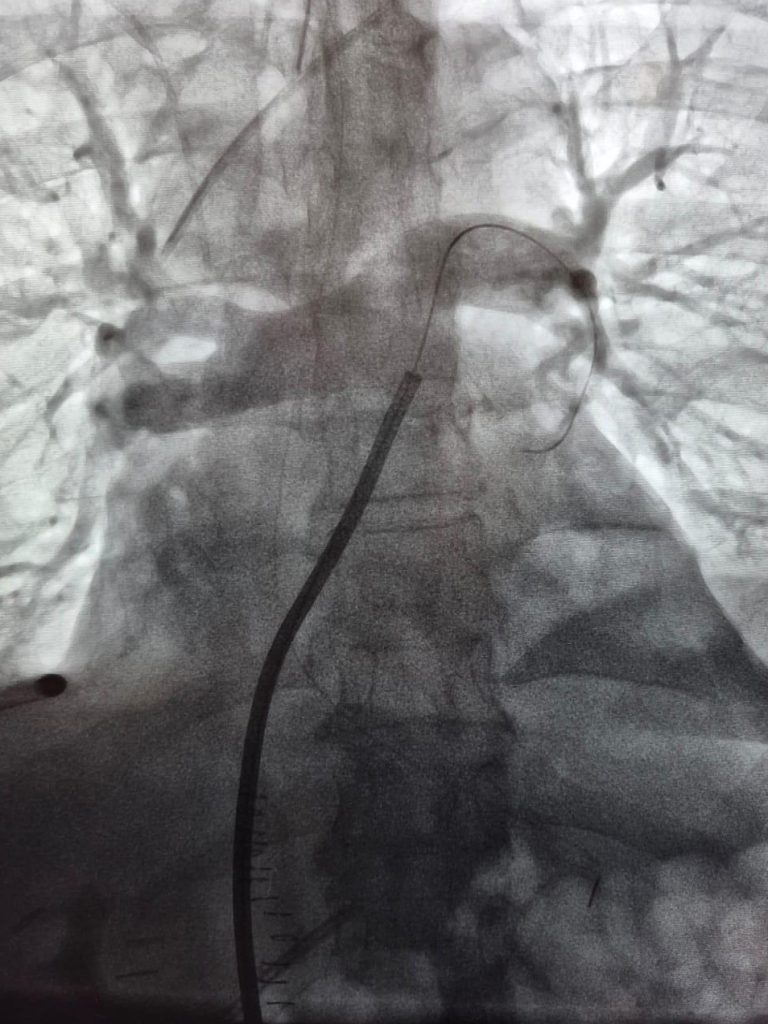

La trombectomía mecánica endovascular es una técnica mínimamente invasiva que permite extraer directamente un coágulo desde la arteria pulmonar. A través de una punción en una vena, generalmente en la pierna o el cuello, se introduce un catéter que avanza por el sistema venoso hasta llegar al corazón y luego a la arteria pulmonar, donde se encuentra la obstrucción. Una vez posicionado el dispositivo, se aspira el trombo, despejando el flujo sanguíneo hacia los pulmones de manera inmediata.

La intervención se realizó en el pabellón de Hemodinamia del Hospital de La Serena, utilizando imágenes en tiempo real para guiar el avance del catéter a través del sistema venoso, el corazón, hasta llegar a la arteria pulmonar. Este control es fundamental para asegurar precisión durante la navegación intravascular y evitar complicaciones. En este contexto, la coordinación entre los cardiocirujanos y cirujanos vasculares fue clave para el éxito del procedimiento, integrando experiencia en técnicas endovasculares con conocimiento en anatomía cardíaca y manejo de pacientes críticos.